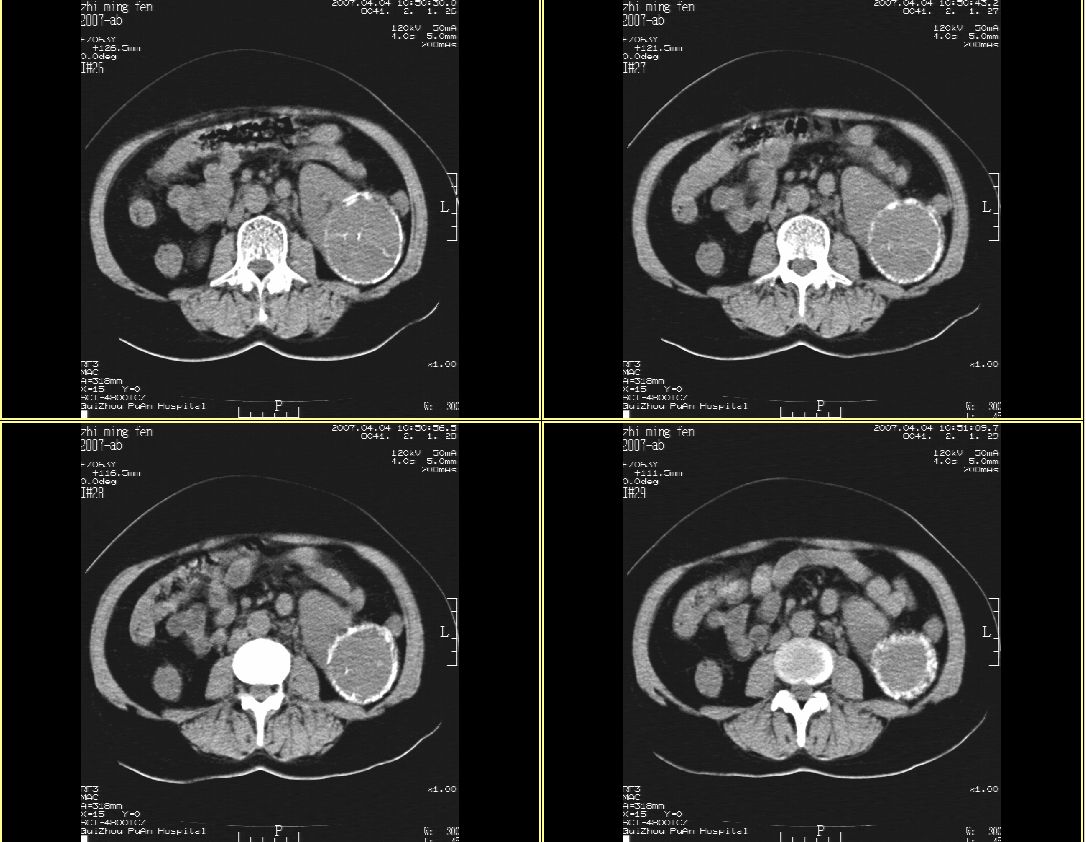

以下是引用hhcckk在2007-4-9 9:18:00的发言:[br]我认为就是一个病灶,病灶上端密度较均匀,下方有明显的钙化,部分呈不完全的环状,考虑肾癌[br]1、肾癌的特征性ct表现为肾实质的占位,局部隆起外突[br]2、肿瘤内的钙化常见,多发生在肿瘤内部,也可以在肿瘤周边呈弧型或不完全的环行钙化[br]3、最常见的三大症状,血尿,腰痛,包块此病人也较符合,增强吧